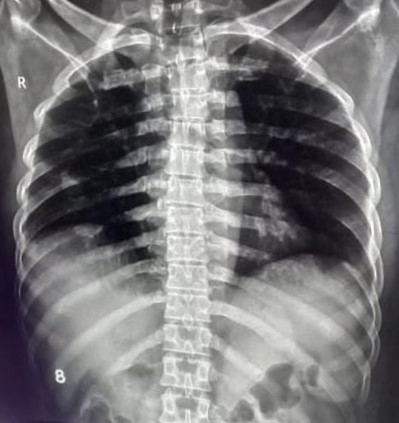

| 173 | IGGMC, Nagpur, Nagpur | P2 | 29-4299 | Vijay Parate | Consent taken on Paper | 50 Yrs. |

Provisional Diag : PTB Follow-Up

Final Diag : ? |

TB Case (Confirmed) | Bilateral Infiltration With Right Sided Upper Zone Cavity | Abnormality visible on x-ray |